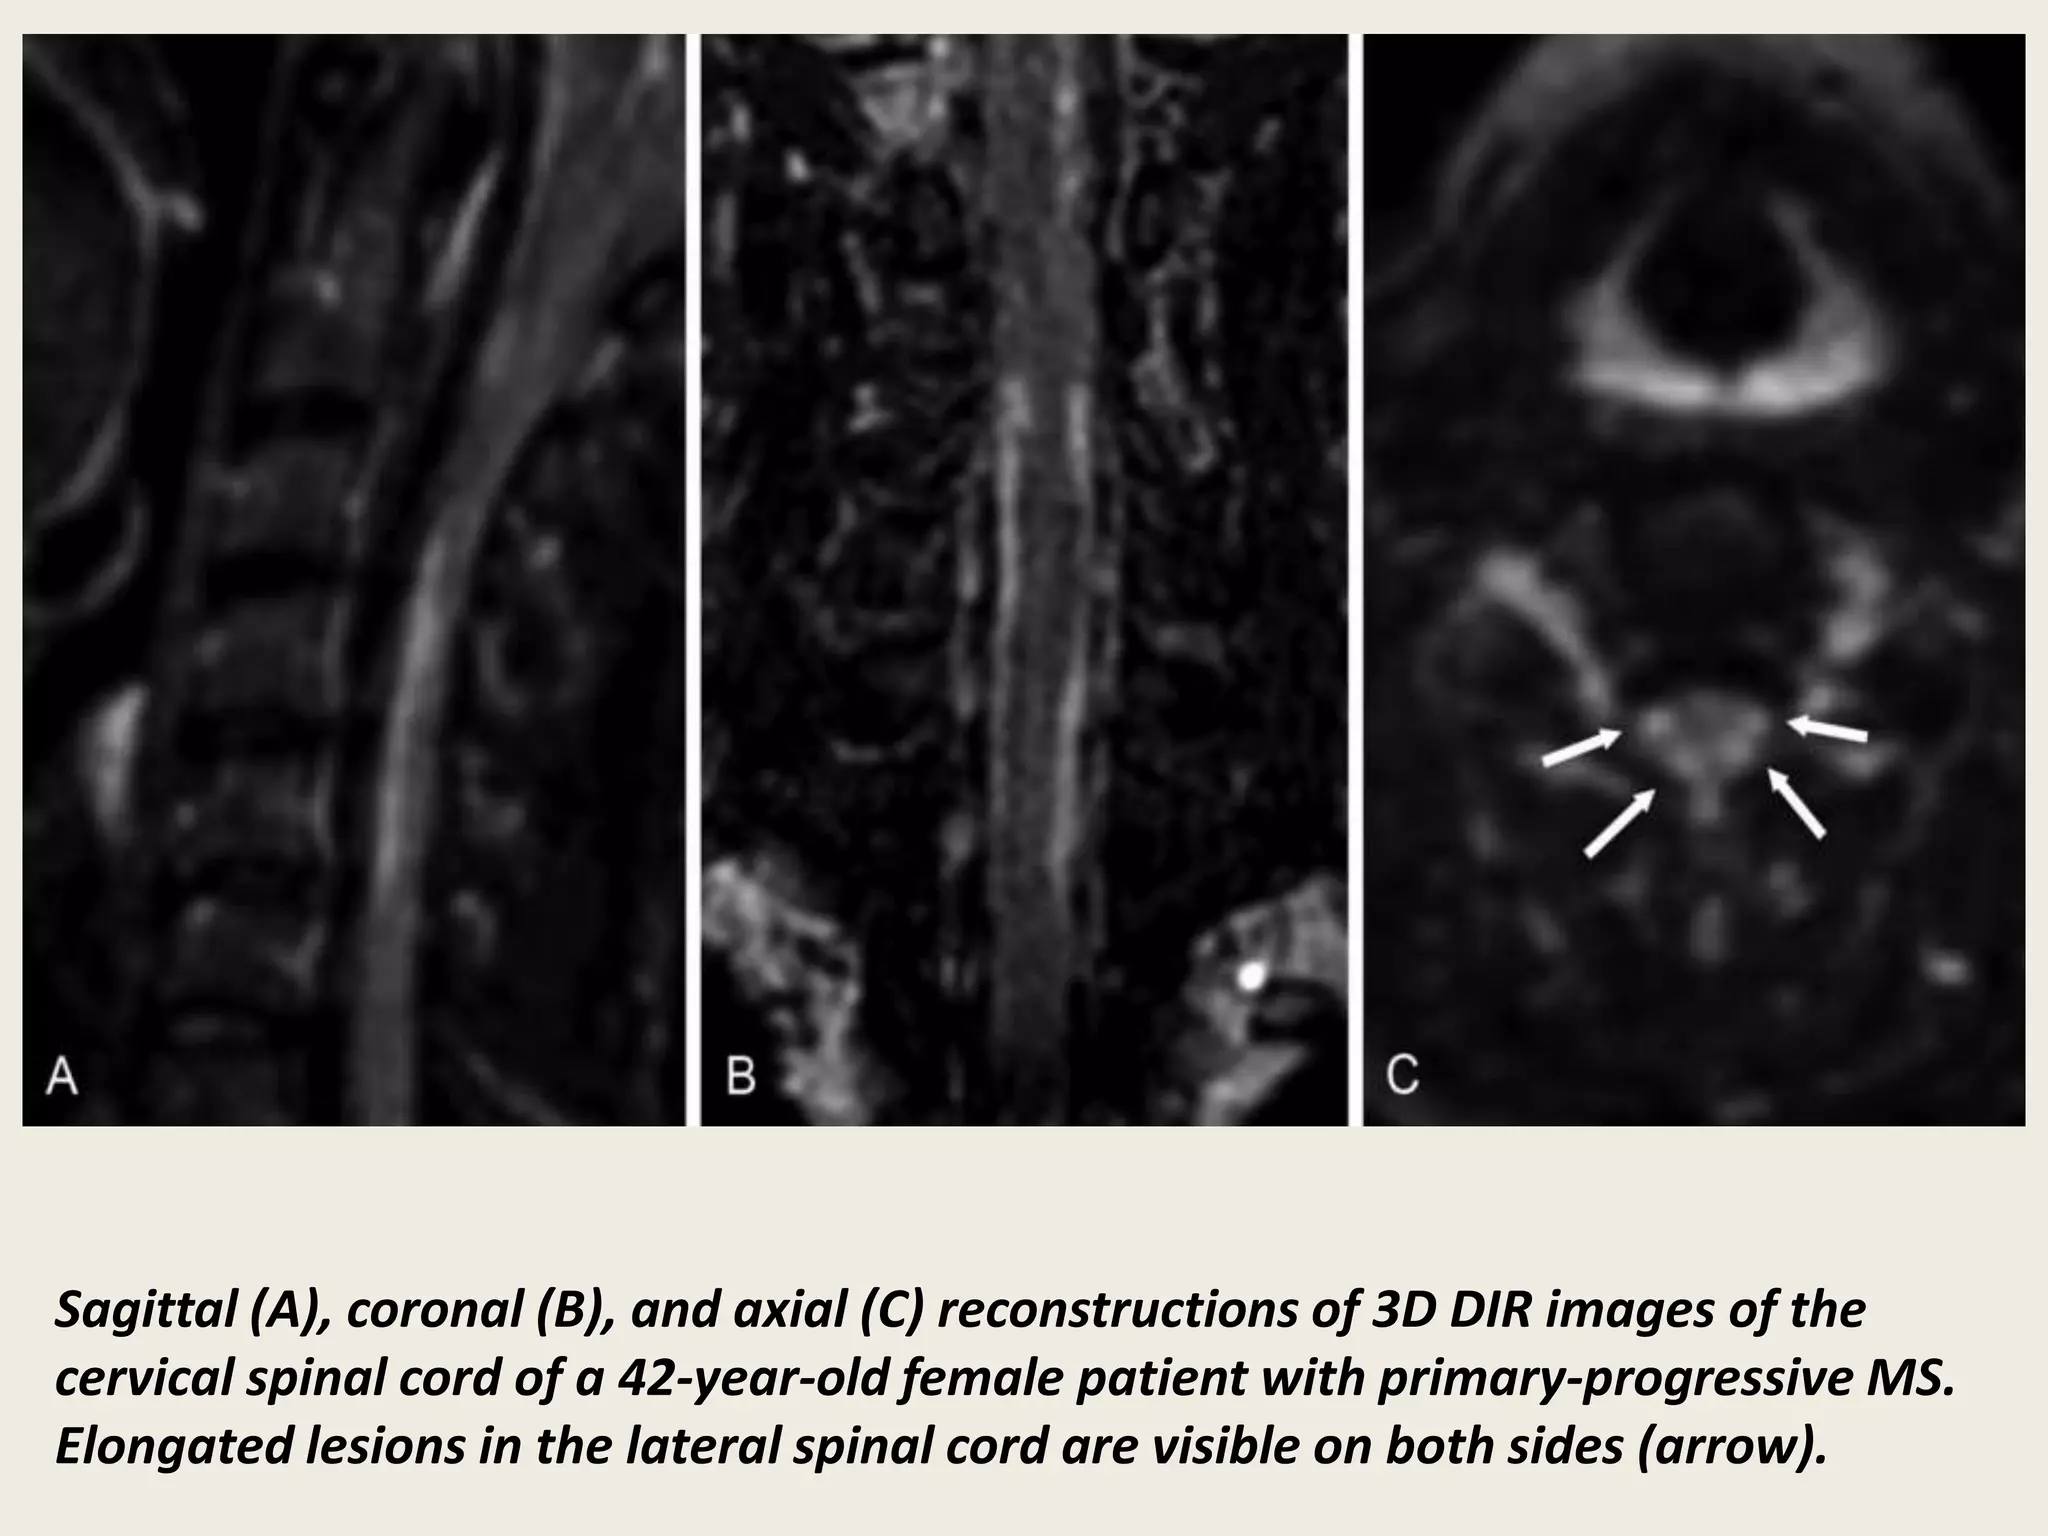

Sagittal (A), coronal (B), and axial (C) reconstructions of 3D DIR images of the

cervical spinal cord of a 42-year-old female patient with primary-progressive MS.

Elongated lesions in the lateral spinal cord are visible on both sides (arrow).